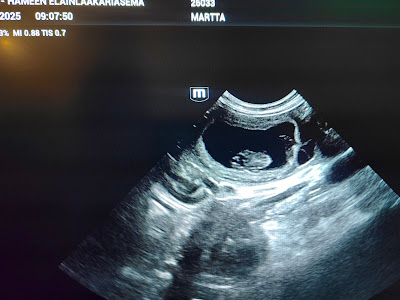

Q-pentueen tulo on varmistettu!

Raappavuoren Murheenkryyni kävi eilen tiineysultrassa ja ell Kaarina Leikas, Päijät-Hämeen Eläinlääkäriasema totesi sen tukevasti tiineeksi.

Raappavuoren Q-pentueen odotetaan putkahtavan maailmaan viikolla 35 ja siten se on viikolla 42-43 luovutusiässä. Kiitos Leipolat mahtavasta yhteistyöstä 💖